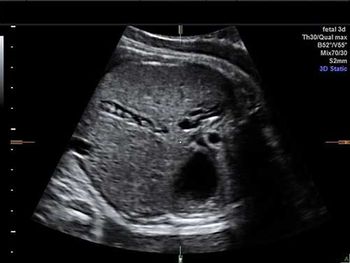

Challenge your anatomy knowledge; what body part is this 3-D image showing?